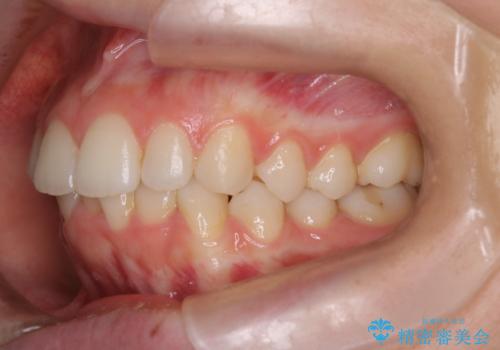

【インビザライン】前歯のガタガタをなおしたい。

- 前歯の凸凹を主訴に来院されました。

インビザラインにて奥歯の遠心移動を行いながら、前歯のガタガタを改善することができました。